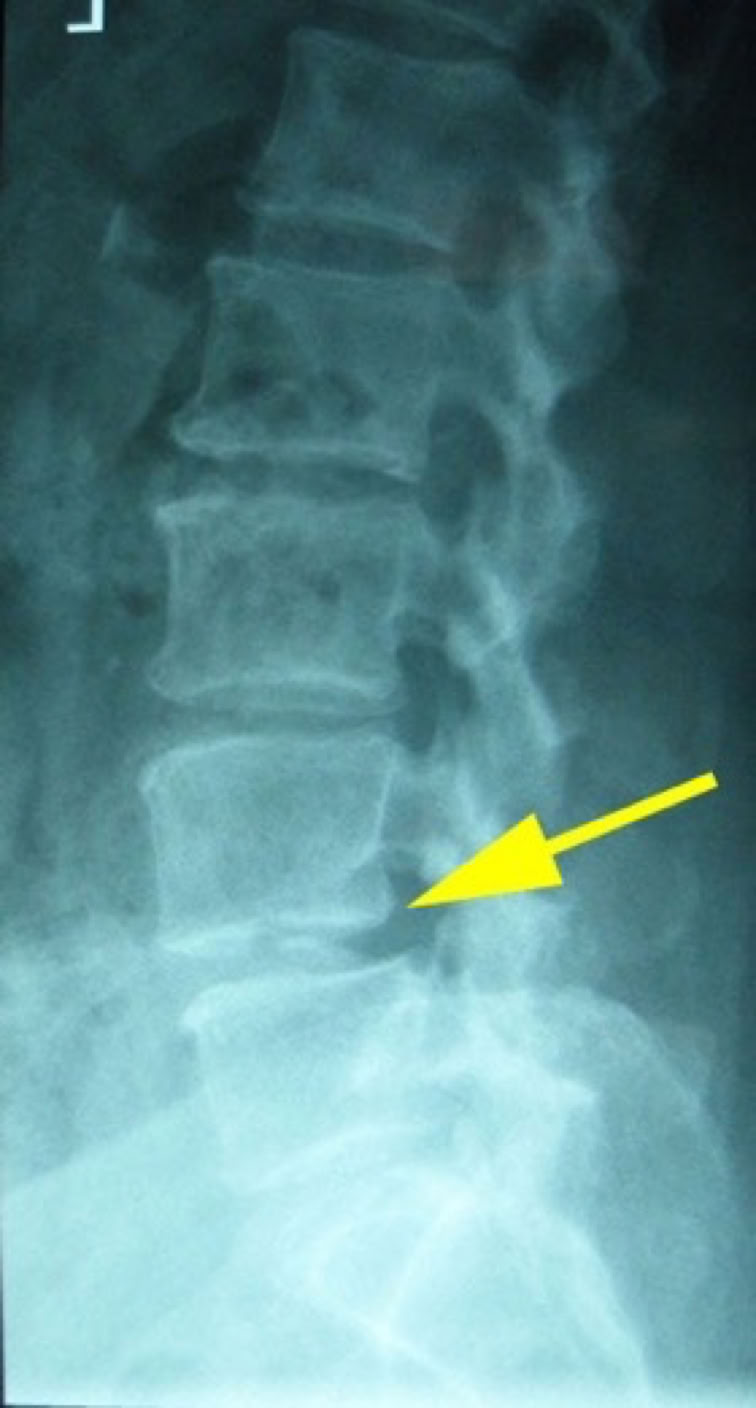

CT was ordered and shown Spinal Canal Stenosis at L4 5, and a left-sided disc prolapse with impingement of the left L4 root.